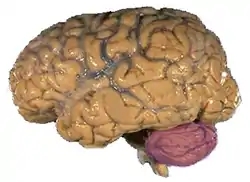

More persistent intention tremors are often caused by damage to certain regions of the brain. Their most common cause is damage and/or degeneration in the cerebellum, the part of the brain responsible for motor coordination, posture, and balance, and especially fine motor movements. When the cerebellum is damaged, a person may have difficulty executing a fine motor movement, such as attempting to touch one's nose with one's finger. One common way for the cerebellum to become damaged is through the development of cerebellar lesions.[13] The most common site for cerebellar lesions that lead to intention tremors has been reported to be the superior cerebellar peduncle, through which all fibers carrying information to the midbrain pass, and the dentate nucleus, which is also responsible for linking the cerebellum to the rest of the brain.[3] Alcohol abuse is one typical cause of this damage to the cerebellum. The alcohol abuse causes degeneration of the anterior vermis of the cerebellum. This leads to an inability to process fine motor movements in the individual and the development of intention tremors. In MS, damage occurs due to demyelination and neuron death, which again produce cerebellar lesions and an inability for those neurons to transmit signals.[13] Because of this tight association with damage to the cerebellum, intention tremors are often referred to as cerebellar tremors.[1]